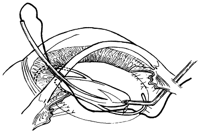

硝子体出血や眼内炎や黄斑前膜など白内障同時硝子体手術(左)や白内障のチン氏帯脆弱症例に対する眼内レンズ縫着術(右)などを行っております。

その他CTR手術(左)・瞳孔形成術・眼内レンズ入替術・裂孔閉鎖術・Add-onレンズ挿入術・眼内レンズ回転術など手術をいろいろなデバイスや術式で行っております。